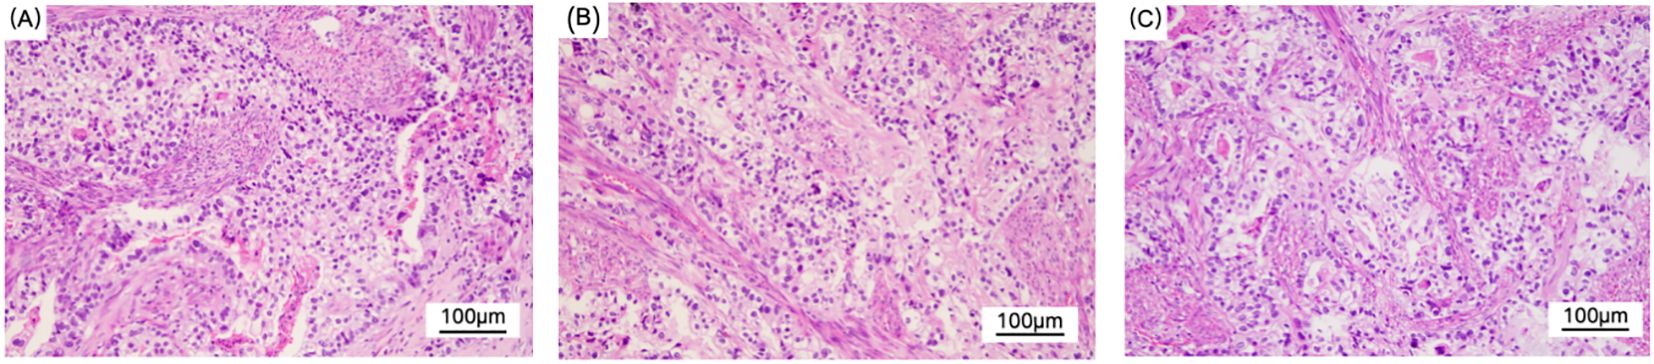

The size of the removed uterus was approximately 8 cm x 8 cm x 2 cm. A rough area measuring 6 cm x 5.5 cm was found in the uterine cavity, characterized by tough gray matter that visibly invaded the entire layer. Additionally, a mass measuring 2.5 cm x 2.1 cm was identified in the uterine cavity, exhibiting gray, white, and red sections with a slightly tough consistency. The tumor invaded the right pelvic peritoneum but did not involve the lymph nodes. According to the FIGO (International Federation of Obstetrics and Gynecology) staging system, this case is classified as Stage IIIB. Microscopically, the main type of cancer was adenocarcinoma. In some areas, the cytoplasm of the tumor cells was transparent, and nuclear/paranuclear vacuoles could be observed, presenting an adenoid or sieve-like arrangement. Nuclear mitotic figures were common (Figure 3). Based on the morphology and immunohistochemical results, it was considered a mixed endometrial-like carcinoma. Some of the tumors were suspected to have differentiated into yolk sac tumors, invading the entire layer of the uterine body muscle wall. Many vascular tumor thrombi could be seen, invading the cervical canal fibromuscular layer (about 1/2 layer), involving the right pelvic peritoneum and the right ovarian vessels, but not the bilateral parametrial tissues or lymph nodes. Immunohistochemistry showed AFP (foci+), SALL4 (+), GPC3 (+), SATB2 (+), CDX2 (+), Villin (+), Pax-8 (-), Vimentin (-), CK7 (in a small part +), CK20 (+), CD10 (+) (Figure 4).

Figure 3. Figure (A–C) show the light microscopic appearance of YST. Hematoxylin and eosin (H&E), original magnification × 200.The main type is adenocarcinoma. Some tumor cells have clear cytoplasm, and nuclear/proximal nuclear vacuoles can be observed in figure (B). They are arranged in an adenoid or sieve-like pattern, and mitotic figures are common. Considering the morphology and immunohistochemical results, it is considered a mixed endometrial-like carcinoma. Some of the tumors are suspected to have differentiated into yolk sac tumors.